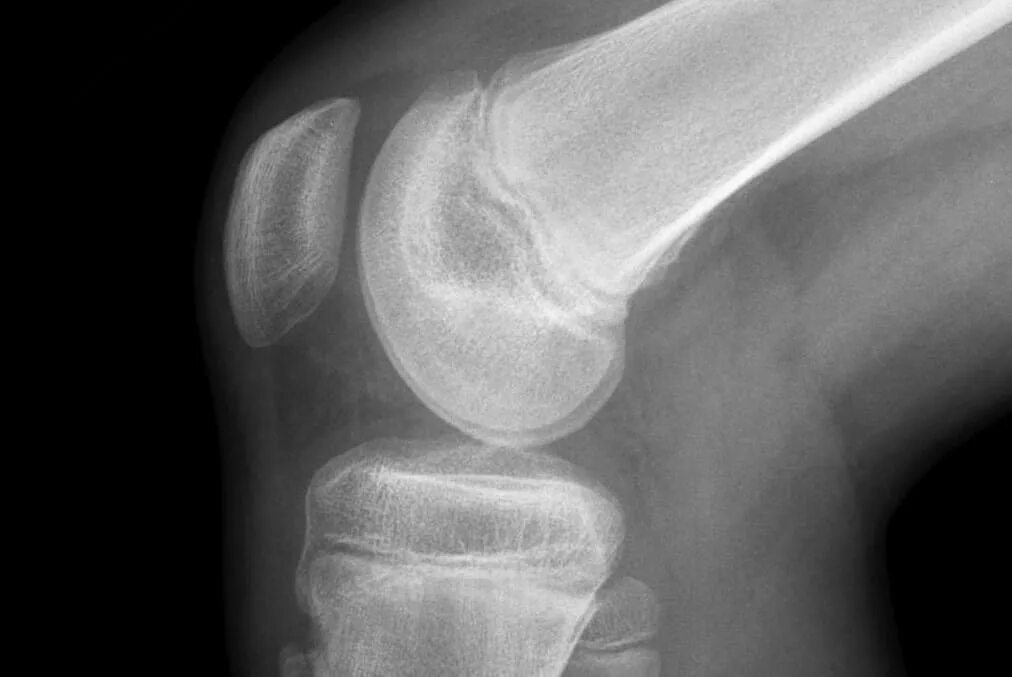

Болезнь осгут шляттера